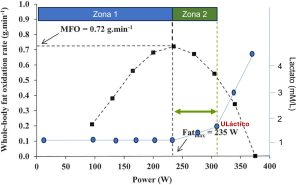

Más allá de los cambios en la composición corporal, los efectos negativos del clembuterol resultaron especialmente relevantes. Se documentó una reducción del VO₂máx del 7% y una disminución del 4% en la capacidad de ejercicio, sin mejora alguna en la potencia de sprint. Esto implica que, pese a inducir hipertrofia muscular, el clembuterol compromete de forma significativa la aptitud cardiorrespiratoria. Curiosamente, no se detectaron cambios en la masa ventricular izquierda, el volumen sanguíneo intravascular ni la masa de hemoglobina, lo que sugiere que la disminución del VO₂máx se debe a mecanismos periféricos relacionados con la capacidad oxidativa del músculo y no a limitaciones centrales del sistema cardiovascular.

De hecho, los análisis en las biopsias musculares mostraron un descenso en la actividad de la enzima 3-hidroxiacil CoA deshidrogenasa (HAD) y una reducción en la abundancia del complejo V de la cadena de fosforilación oxidativa, indicando una represión de la capacidad oxidativa mitocondrial. Estos hallazgos coinciden con estudios en animales, donde se observó una disminución de enzimas oxidativas y alteraciones en la función mitocondrial tras el uso de clembuterol. En consecuencia, los efectos adversos parecen estar mediados por un deterioro en la capacidad del músculo para utilizar oxígeno de manera eficiente durante el ejercicio.